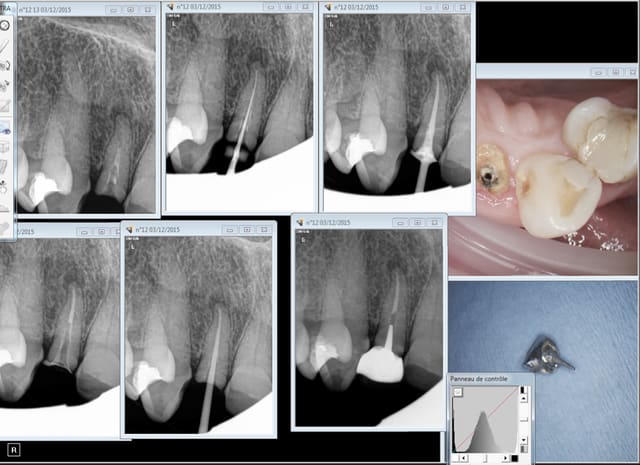

UN exemple de RTE

dépose inlay+couronne en 2009

retraitement sous digue indispensable(même sur dents antérieures la digue ce n'est pas pour faire jolie,c'est pour permettre à l'hypochlorite de rester à demeure tout le long du retraitement;il faut que çà "baigne" pour avoir une chance de

guérison apicale)

ici traitement sous hypo+digue +r-endo;il y a un dépassement léger au périapex

en 2015 guérison apparente du périapex(1h30 de retraitement!)

la dépose de l'inlay avec des ultrasons;désobturation acétate éythyle r-endo gutta compactage mac spadden

5eme photos en2009 et 2010;la dernière en 2015